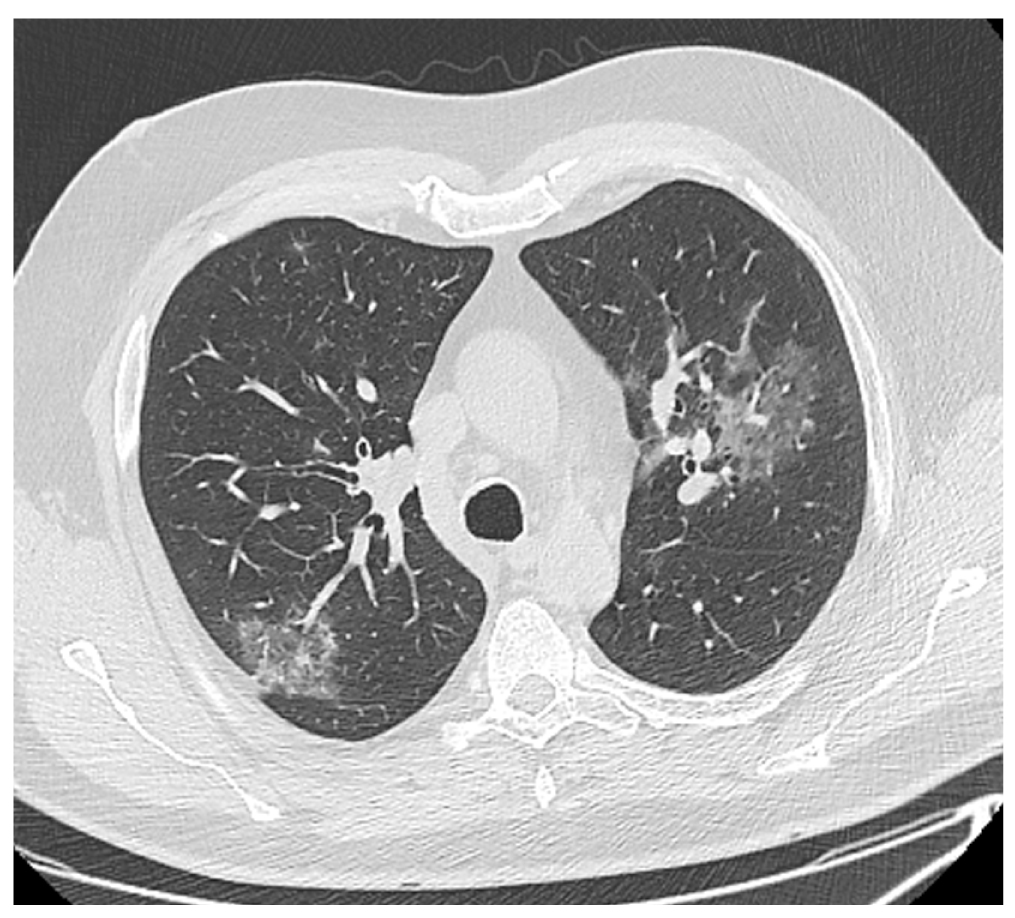

Данные компьютерной томографии (КТ) свидетельствовали о пневмонии второй степени тяжести (рис. 1). Результаты теста на COVID-19 методом полимеразной цепной реакции (ПЦР) были положительными. Сопутствующие заболевания представлены гипертонической болезнью (ГБ), тромбоэмболией легочной артерии (ТЭЛА) от 2019 года и стенозом позвоночного канала на уровне L5–S1 (рис. 2).

Рис. 1. Пациент В., 58 лет: компьютерная томограмма органов грудной клетки свидетельствует о пневмонии средней степени тяжести (КТ-2). / Fig. 1. Patient V., 58 years old: сomputed tomography of the chest organs indicates moderate pneumonia (CT-2).

Объем поражения легких (КТ) в связи с COVID-191 | КТ-2 | КТ-3 | КТ-2 | |

Степень специфических изменений в легких, по радиологическим данным, оценивалась как КТ-2 (см. табл. 1; рис. 5). Течение инфекции было отягощено сопутствующей болезнью Паркинсона, гипертонической болезнью, фибрилляцией предсердий, перенесенным ишемическим инсультом от 2020 года, протяженным стенозом позвоночного канала на уровне L1–L5. За время пребывания в инфекционном отделении пациент получал терапию ГКС, тоцилизумабом, антибактериальную терапию меропенемом, линезолидом. Проводилось переливание плазмы крови с антителами к COVID-19.

Рис. 5. Пациент Л., 75 лет: компьютерная томограмма органов грудной клетки свидетельствует о пневмонии средней степени тяжести (КТ-2). / Fig. 5. Patient L., 75 years old: computed tomography of the chest organs indicates moderate pneumonia (CT-2).